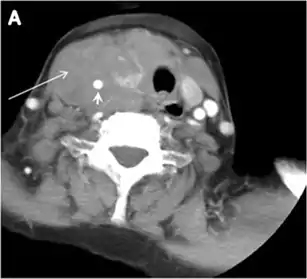

Fig. 7. A 51-year-old female patient post total thyroidectomy for PTC with elevated thyroglobulin measurement. an Axial non-enhanced CT scan of the neck at the level of the thyroid bed demonstrates a well-defined, rounded, homogenously dense soft tissue situated between the trachea and left internal jugular vein (white arrow). b Transverse ultrasound image of the neck demonstrates a well-defined, homogeneous, hypoechoic soft tissue nodule measuring 6 mm (white arrow) with no detected micro-calcifications. Biopsy showed a predominantly residual normal thyroid tissue with micro-foci of PTC.[1]

Fig. 8. A 48-year-old male patient post total thyroidectomy with PTC recurrence. a Transverse greyscale ultrasound of the neck demonstrates a left thyroid bed heterogeneous, predominantly hypoechoic irregular lesion with calcifications (white arrow). b A spot image of iodine 123 total body scan of the neck demonstrate a focus of abnormal radiotracer uptake at the left thyroid bed (Black arrows) between the annotated markers. c Enhanced axial CT scan of the neck demonstrates an enhancing large left thyroid bed mass (white arrow) with no calcifications. The lesion exerts a mass effect on the oesophagus (black arrow) and is inseparable from the trachea.[1]